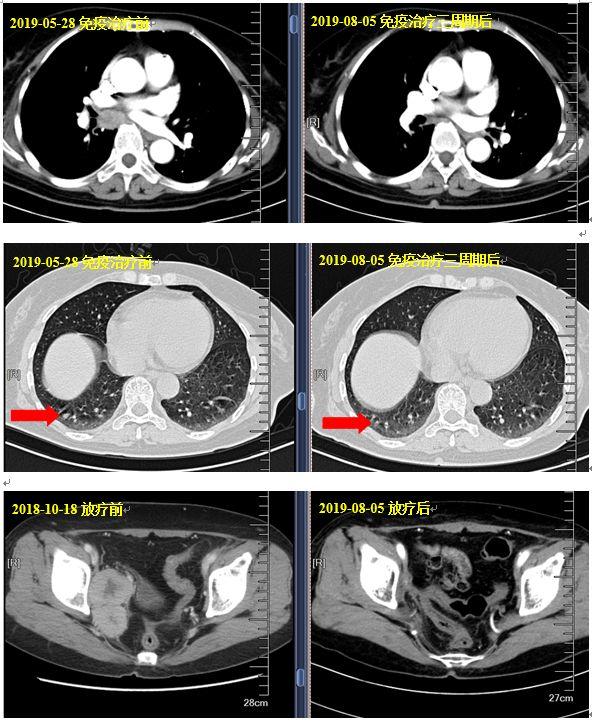

盆腔及外阴病灶放疗同步伊立替康化疗四次:照射野内有效,照射野外肿瘤进展。

随后行伊立替康+安罗替尼方案化疗五周期,期间患者因无法耐受安罗替尼未遵医嘱规律用药。CT示纵膈肺门淋巴结较前增大,右肺出现新发病灶,血CA125、CA153升高,评估疗效为PD。

采用新抗原个体化纳米疫苗联合PD-1抗体治疗:行环磷酰胺+个体化疫苗+信迪利单抗方案治疗3周期,并予注射疫苗总共六次,未见明显不良反应。可测量病灶:纵膈肺门淋巴结、右肺小结节(原有的盆腔、外阴病灶自放疗后维持CR)。疗效评价:接近CR,血肿瘤指标均降至正常。